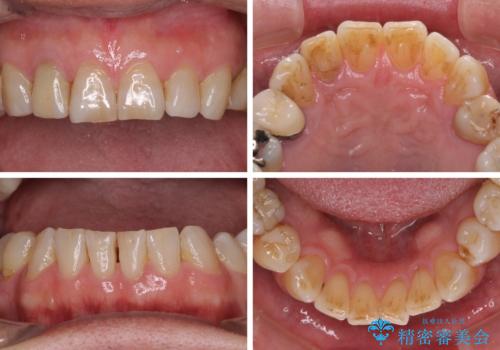

憧れの白い歯に 全顎セラミック治療

- 60歳を越え、黄ばんだ前歯をセラミッククラウンできれいな口元にしたいとのことで来院された患者様です。

診察したところ、前歯は反対咬合であり、その影響で抜歯が必要な奥歯があることが分かりました。

抜歯が必要な奥歯は、インプラント並びにブリッジにより補綴を行い、上下前歯は反対咬合を改善させるように補綴治療を行うこととしました。

健全な歯を削ってセラミッククラウンに置き換えることは、本来避けるべき治療と考えますが、今回は①患者様が60歳を越えていること、②要改善の咬合により抜歯が必要な奥歯があること、③反対咬合の前歯改善の手段としてセラミック治療が選択肢にあることなどから、全顎的なセラミック治療を行うこととしました。